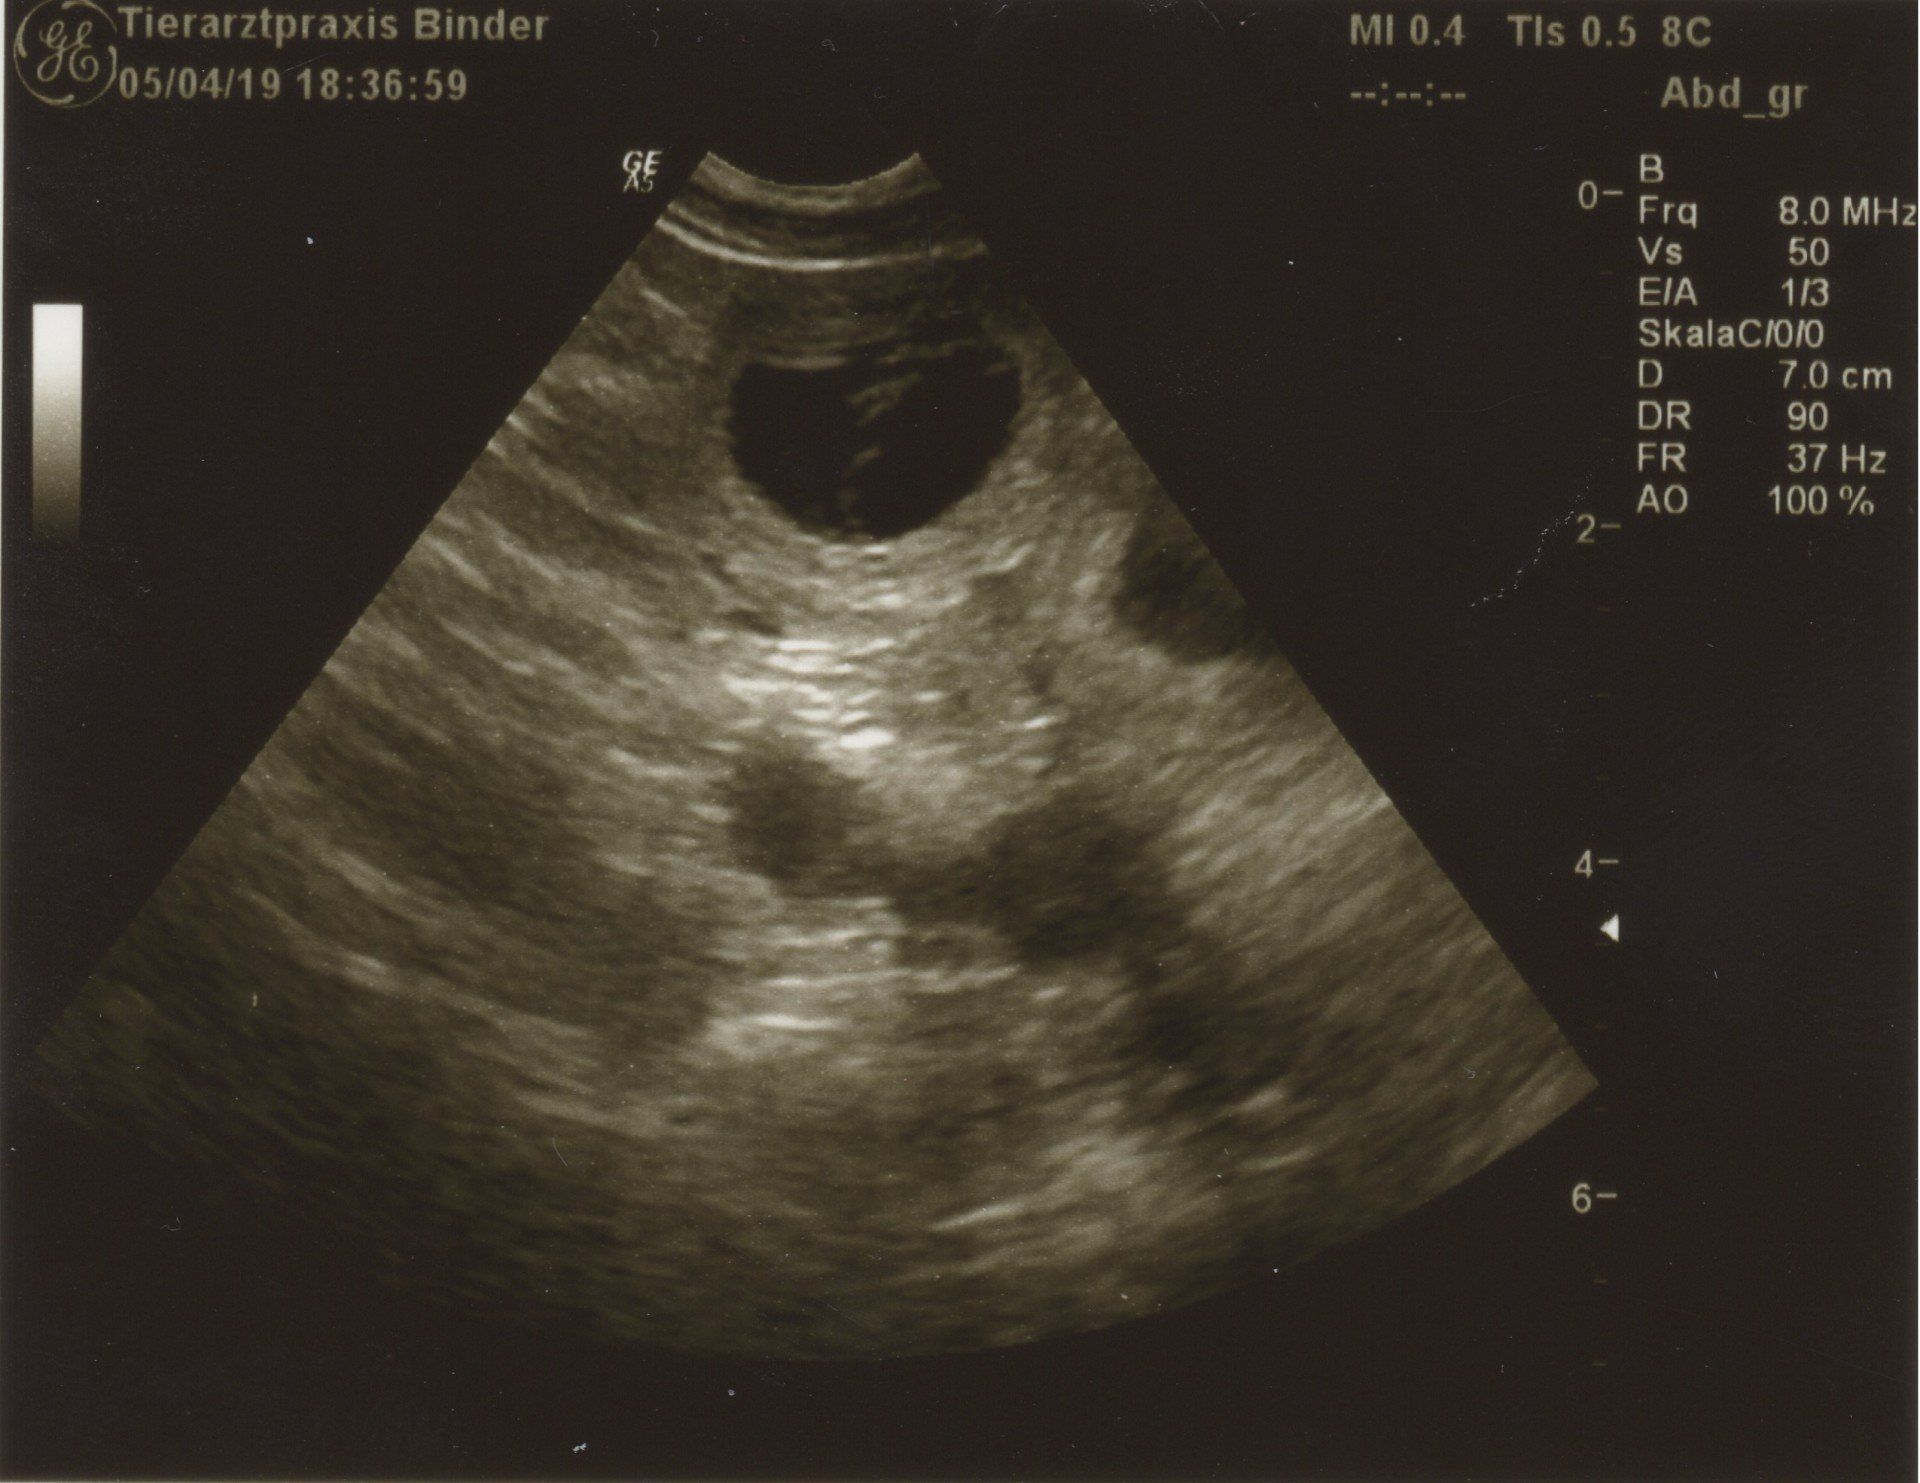

05.04.2019 Woche 4 25.Tag von ca.63Tagen

Tag 25 Ultraschall Untersuchung bei Dr. Binder

05.04.2019

Wir waren zur Ulraschalluntersuchung! Ja !